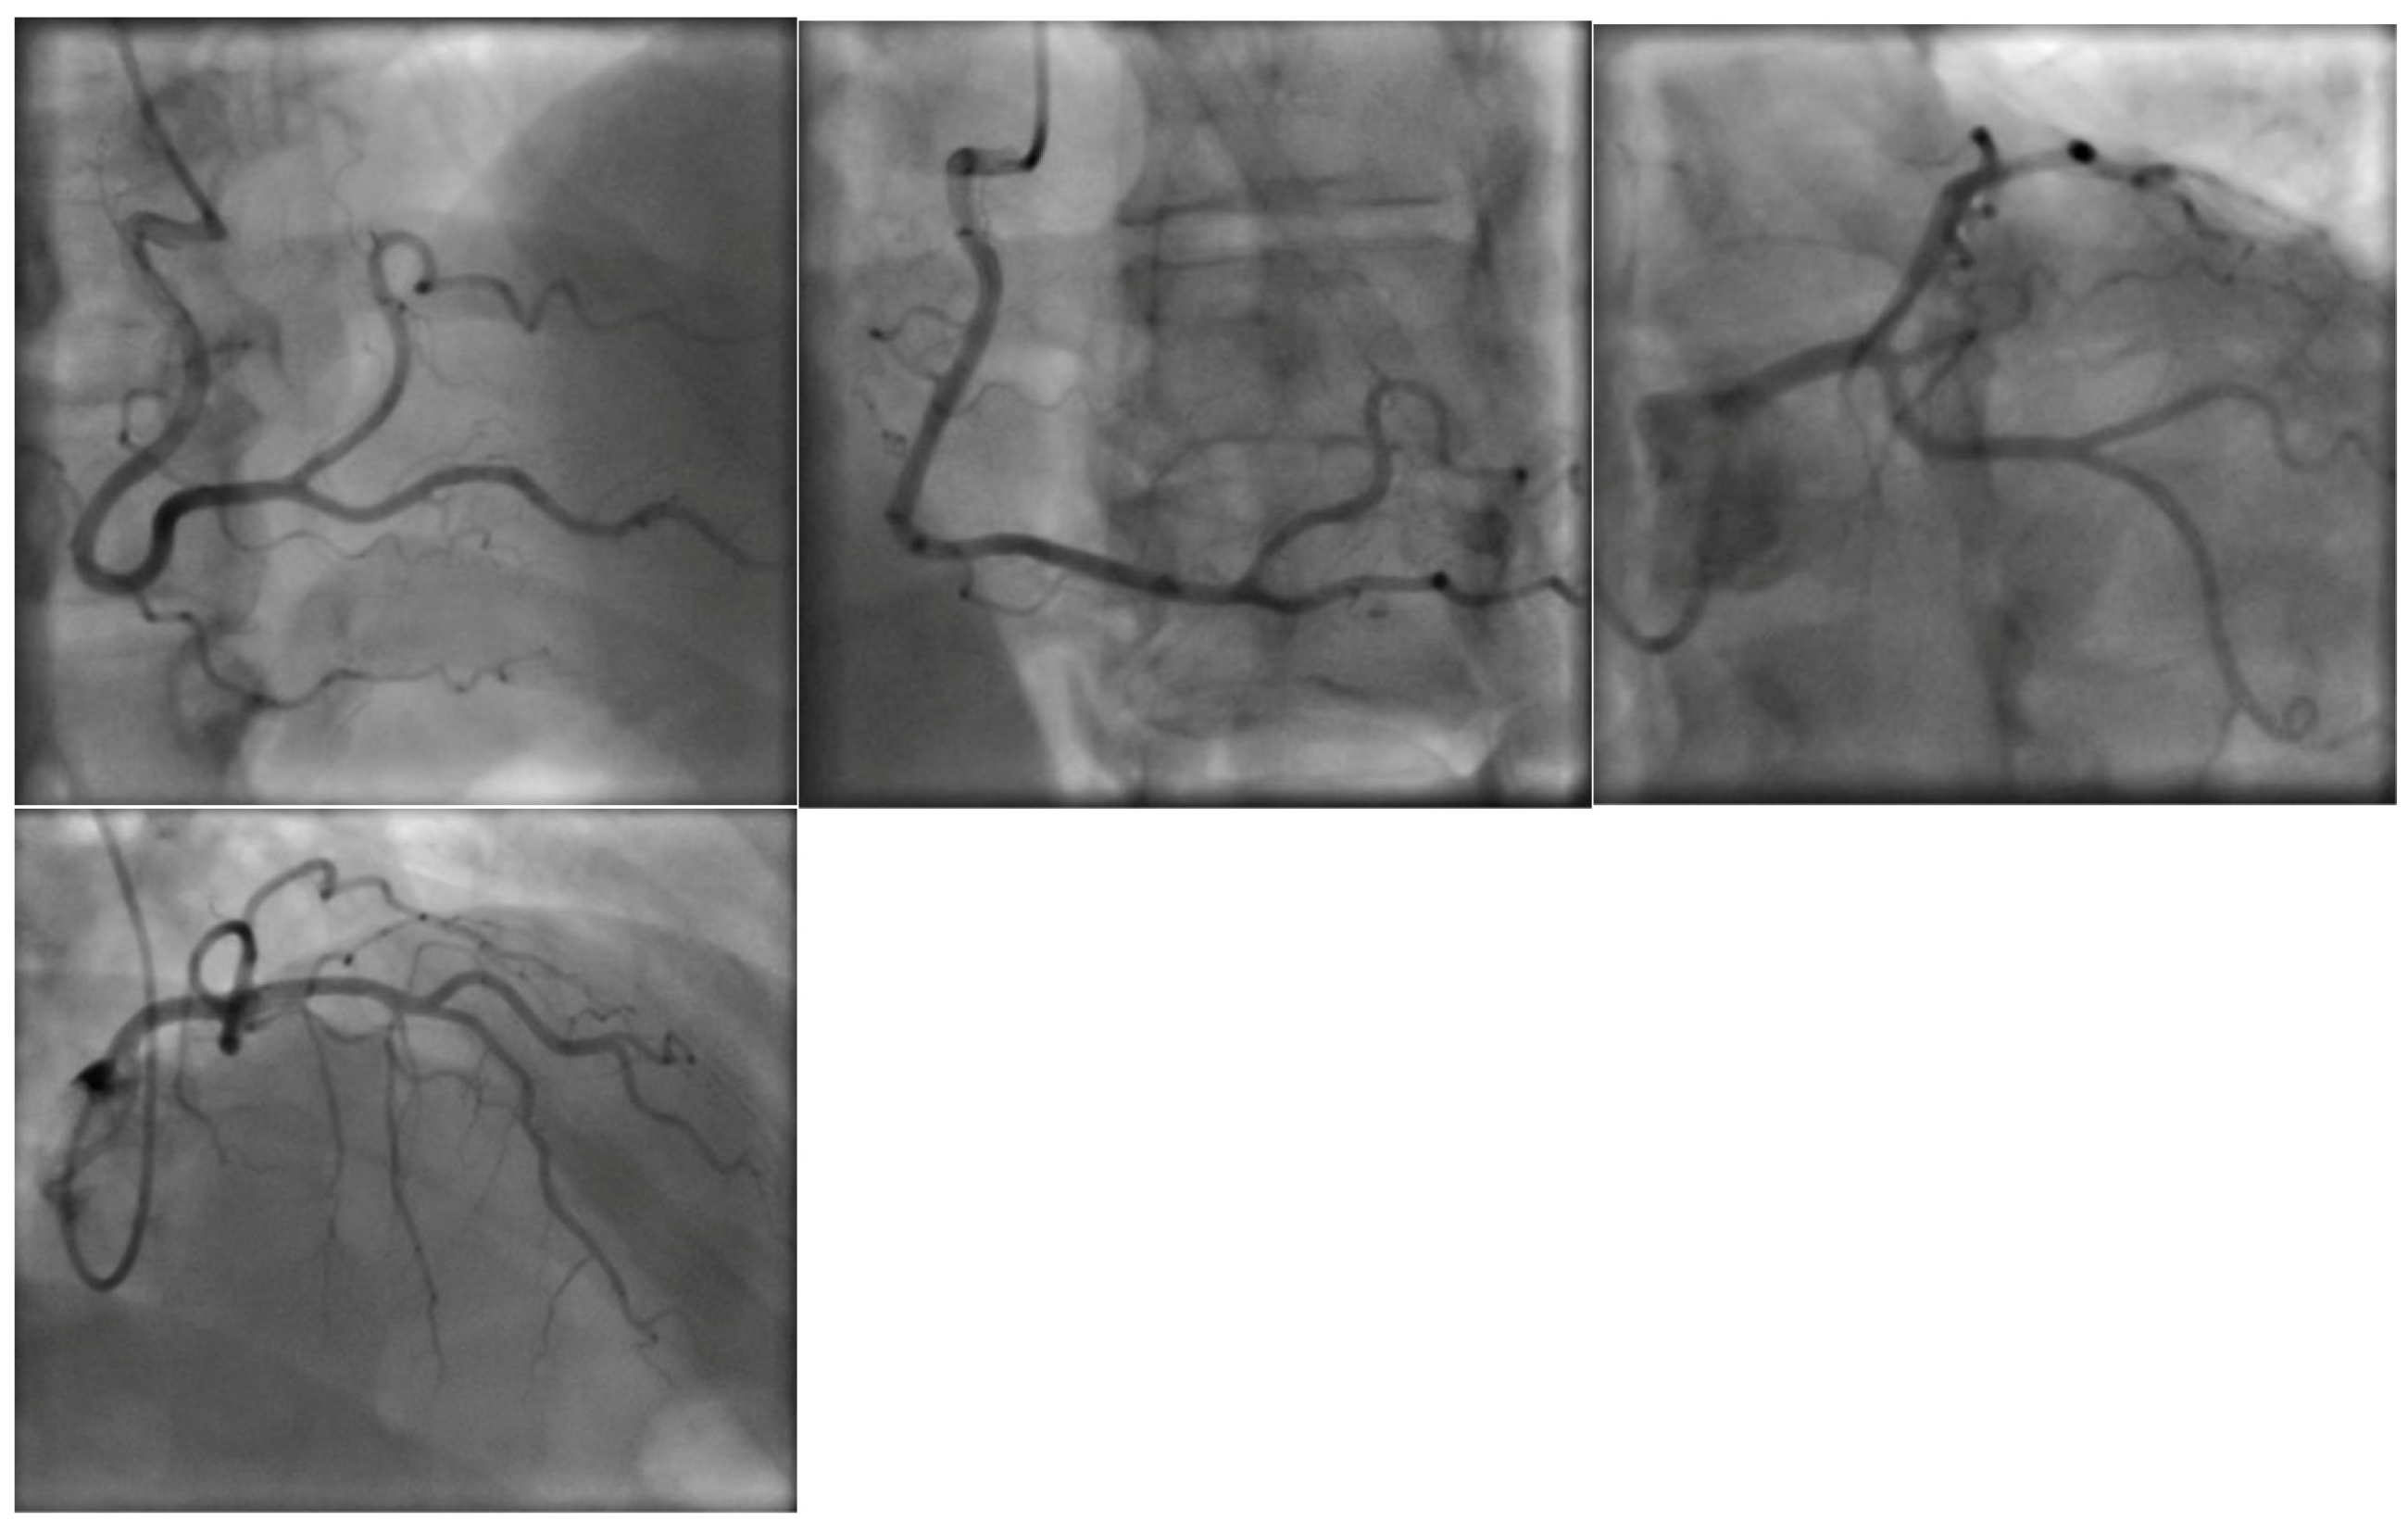

2. Case Presentation